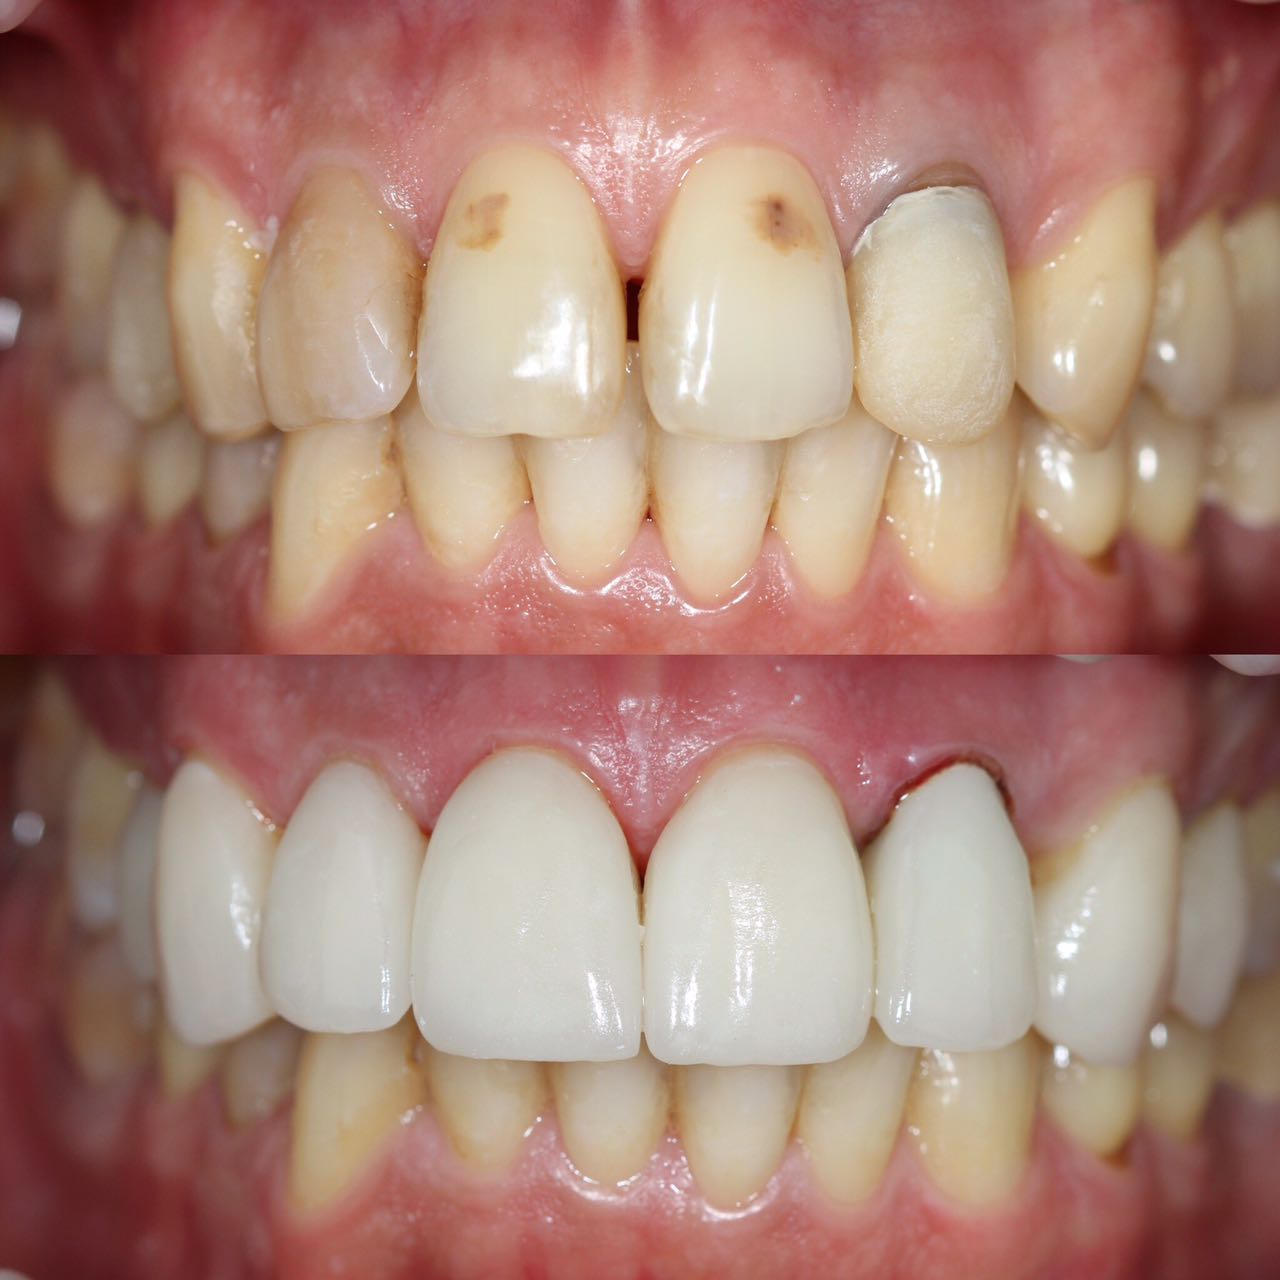

Примеры работ